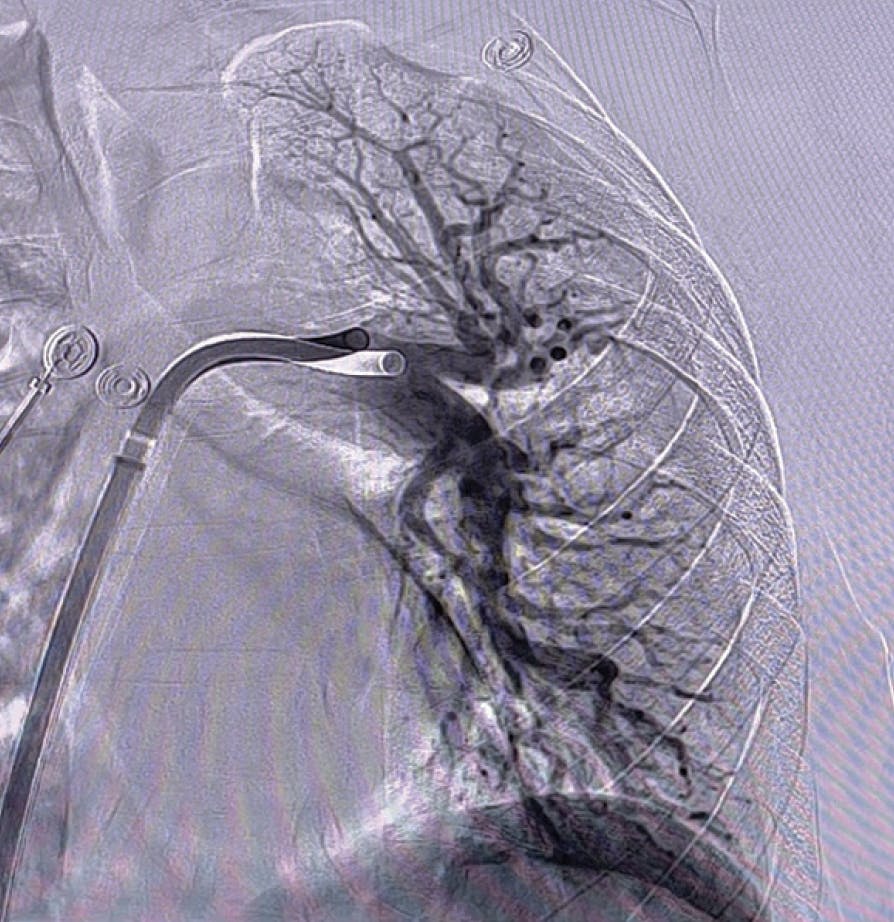

A patient in her early 60s presented with fatigue, sudden onset of sharp chest pain, and shortness of breath. Initial evaluation revealed resting tachycardia of 120 bpm with a BP of 93/80 mm Hg and an oxygen saturation of 84% on room air. Additionally, the patient had elevated troponin and BNP. A CT pulmonary angiogram (CTPA) revealed an extensive thrombotic burden involving all five lobes, with an elevated right ventricular/left ventricular (RV/LV) ratio of 1.3 (Figure 1). Parenteral anticoagulation was administered, and after discussion with the PE response team, she was transferred for advanced therapy. Based on the patient’s symptoms, the decision was made to pursue thrombus extraction with Lightning Flash due to the device’s moderate-bore profile and trackability.

Figure 1. Right and left initial angiograms.

INTERVENTION

Access was achieved in the right common femoral vein (CFV), and initial diagnostics revealed an elevated mean PA pressure of 34 mm Hg. After selection of the right lower lobar PA, the venotomy site was dilated over a wire and a 16-F, 33-cm Gore DrySeal sheath was placed. Under fluoroscopic guidance, a 16-F, 100-cm Lightning Flash XTORQ was advanced into the right PA and two passes were performed. Subsequently, the device was tracked into the left PA and two additional passes were performed. Figure 2 shows the amount of clot extracted. Reassessment of hemodynamics revealed improvement in mean PA pressure from 34 to 17 mm Hg, reflecting an on-table drop of 17 mm Hg. Additionally, selective bilateral pulmonary angiography showed significant improvement in perfusion (Figure 3). By the conclusion of the case, the patient was weaned from FiO2 of 15 L/min to room air.

Figure 2. Clot removed.

Figure 3. Post-thrombectomy right and left angiograms.

A patient in his late 50s presented to the emergency department (ED) with fatigue, shortness of breath, and emesis. The patient had previous medical history of hypertension, diabetes, and anemia. Initial diagnostics showed elevated levels of high-sensitivity troponin I at 482.8 ng/L, a HR of 104 bpm, and oxygen saturation of 91%. A transthoracic echocardiogram revealed mildly dilated RV size with mildly reduced ventricular systolic function. Evaluation of imaging and diagnostics confirmed a submassive saddle PE with right heart strain due to an RV/LV ratio of 1.9 (Figure 1, Figure 2, and Figure 3). The decision was made to pursue mechanical thrombectomy with Lightning Flash for the acute submassive PE.

Figure 1. CTPA showing a submassive saddle PE.

Figure 2. Initial angiogram.

Figure 3. Preprocedural venogram.

Access was obtained in the right femoral vein. The mean PA pressure before thrombectomy was 29 mm Hg. CTPA revealed acute bilateral PE in the bilateral lobar and main PAs (Figure 1). Thrombectomy was performed with the 16-F Lightning Flash device and resulted in < 50 mL of blood loss. A postprocedure pulmonary angiogram revealed successful mechanical thrombectomy with establishment of flow from the PAs to both lungs (Figure 4 and Figure 5). The patient’s HR decreased to 81 bpm, and his oxygen sats increased to 100%. The patient’s final high-sensitivity troponin I levels were measured at 123.8 ng/L. With a minimal 4-day hospital length of stay and no postprocedural complications, this PE procedure with Lightning Flash was successful.

Figure 4. Post-thrombectomy angiogram.